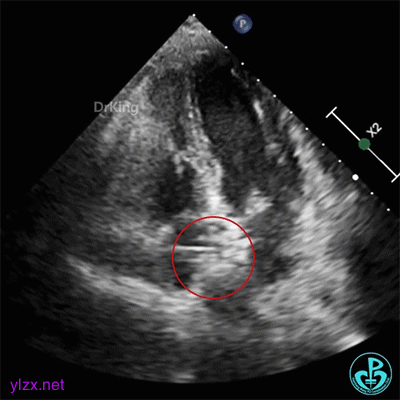

术前经食道超声描述:室间隔连续完整,房间隔中部菲薄,呈瘤样凸向右房面,基底宽约12mm,膨出约8mm。卵圆窝处薄弱,呈纤细线样回声,原发隔与继发隔间见纤细裂隙,入口约0.4mm,出口约0.8mm,卵圆瓣长约20.1mm,原发隔摆动幅度约13mm,继发隔厚约4.5mm,瓦式呼吸后,入口较宽约3.8mm,出口较宽约2.0mm,卵圆瓣左房侧末端迂曲。CDFI裂隙处可见微量左向右过隔血流信号。左心耳显示清楚,内未见异常回声。主动脉内中膜欠光滑,窦部宽约25mm,管腔未见明显狭窄与扩张,CDFI未见明显异常血流信号。各房室腔比例尚可,未见明显节段性室壁运动异常,各瓣膜形态、结构正常,启闭尚可。

经食道超声三维、二维和右心声学造影图像: